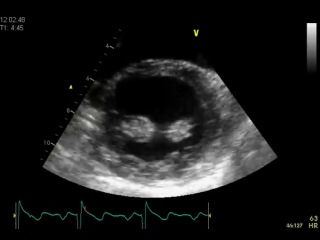

Чтобы жить долго и счастливо, нужно здоровое сердце. Не забудьте регулярно проверять состояние этого важного органа с помощью УЗИ. Ежегодно в России от болезней сердца умирают 1 млн 300 тысяч человек. Ранняя диагностика позволяет существенно снизить риск тяжелых осложнений. Ультразвуковое исследование сердца (УЗИ) сердца, или эхокардиография, – это точный, быстрый и безопасный способ оценки толщины […]